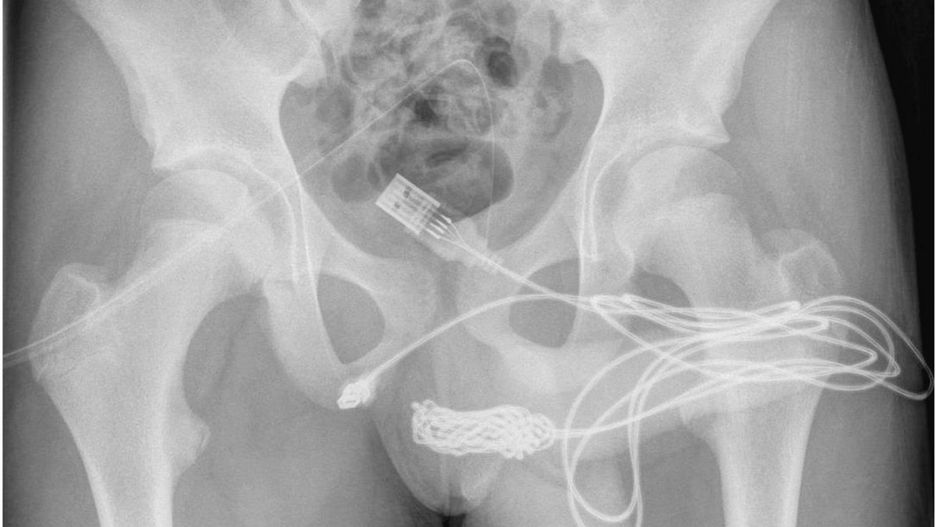

Przewód wewnątrz ciała chłopca poplątał sięPrzewód wewnątrz ciała chłopca poplątał się

15-latek z Wielkiej Brytanii w nietypowy sposób postanowił zmierzyć swojego penisa kablem USB. Przewód zaplątał się wewnątrz ciała nastolatka, przez co chłopak nie mógł go samodzielnie usunąć.

Do sytuacji doszło w listopadzie 2021 roku. Węzły, które utworzyły się na kablu, sprawiły, że młody Brytyjczyk zauważył krew w moczu. Wtedy też jego mama zabrała go do szpitala.

Przez ilość powstałych supełków na kablu, lekarze również nie mogli go usunąć. By wydostać przewód z wnętrza cewki moczowej, chłopak musiał przejść operację. Finalnie oba końce przewodu wyciągnięto przez zewnętrzne ujście cewki moczowej.